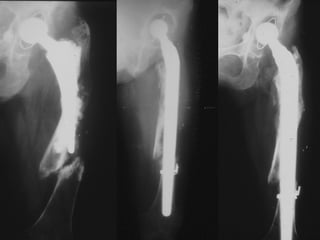

REVISIONI

FINE ANNI 80’

STELO LORD

PROBLEMI

- DOLORE ANTERIORE

di COSCIA

- “STRESS SHIELDING”

IN COMPLESSO, TECNICA

INAFFIDABILE